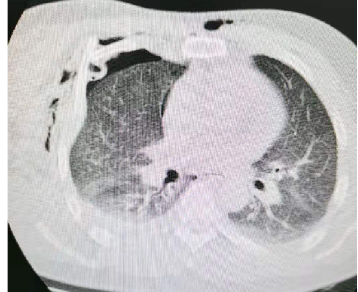

2021年5月12日一病区大交班晨会病区部分病例分享如下: 病例1:多发肋骨骨折合并血气胸。患者因“工作时被机器卷伤致右胸、右肩及右前臂”入院。入院诊断:1、右胸多发性肋骨骨折合并血气胸;2、右桡骨中下段粉碎性骨折;3、右肩胛骨骨折;4、右肺挫伤;5、右侧肩袖损伤;6、右侧肩锁韧带损失伤;7、右侧盂肱韧带损伤。

(血气胸)(2-7肋骨骨折)(肩胛骨骨折) 在全麻+臂丛麻醉下行“右胸3-6肋骨骨折切复钢板螺钉内固定术、胸腔闭式引流术、右桡骨中下段骨折切复钢板螺钉内固定术”。

(术后) 术后4天拔除胸腔闭式引流管。

(术后4天) 刘立春副院长进一步对该患者病情进行了介绍。该患者皮下气肿较多、纵膈也有,对于多发肋骨骨折,应警惕是否存在张力性气胸。刘院长阐述了张力性气胸的应急处理措施,并强调了对于绞轧伤,应注意排除是否存在内脏损伤及神经损伤。